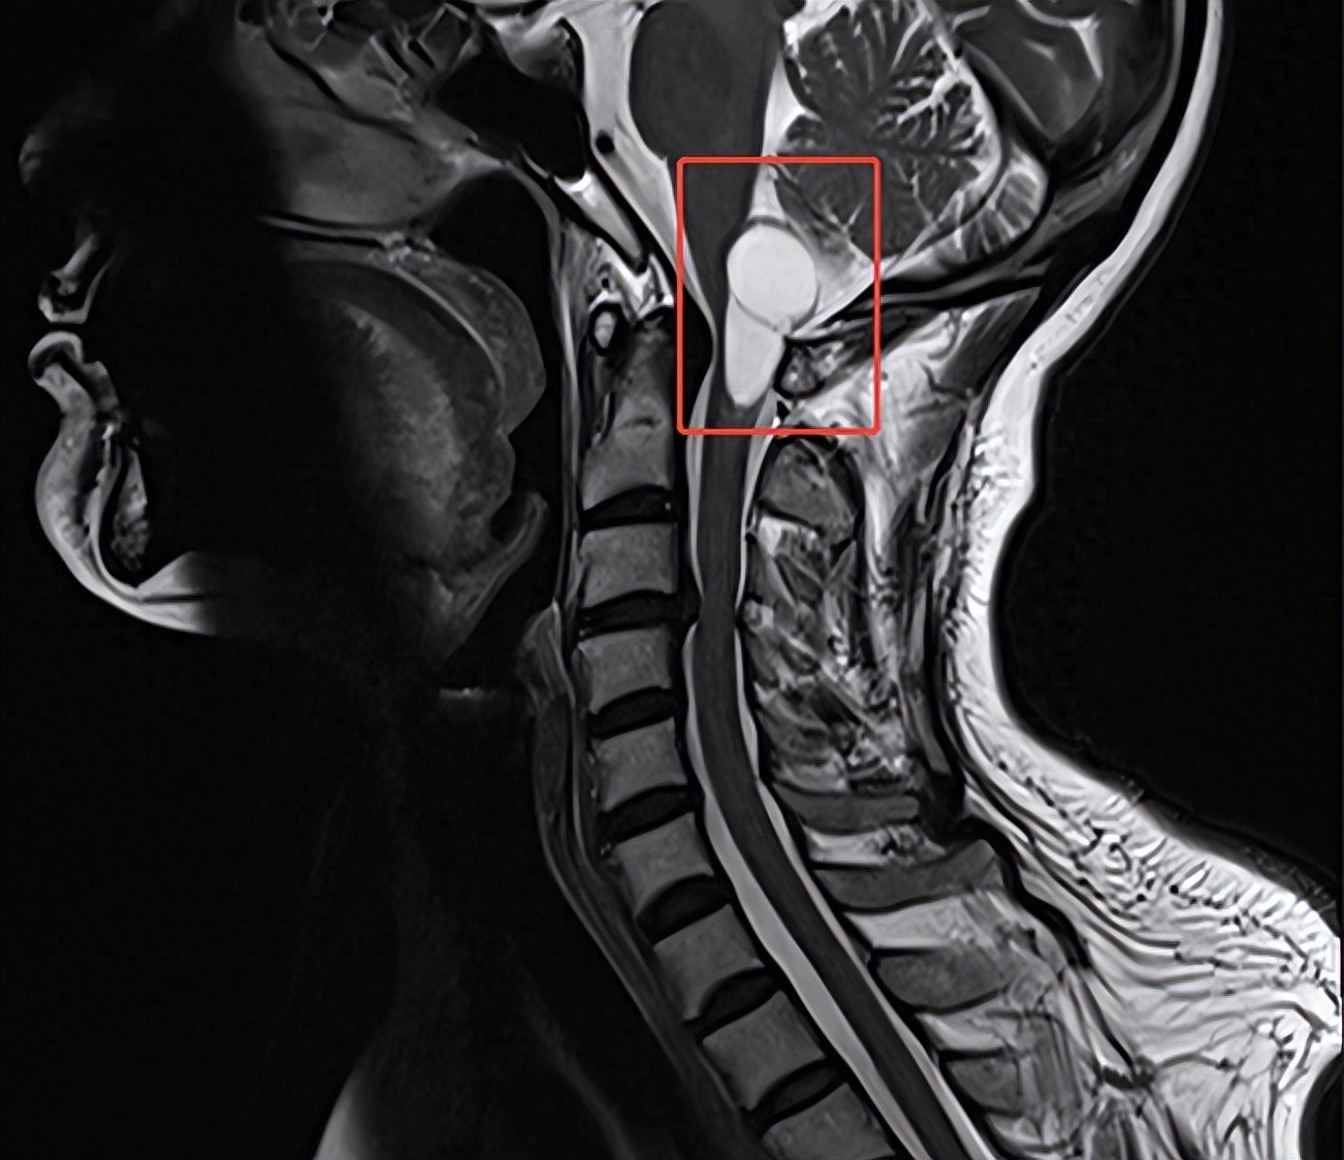

2月3日,62岁的陈女士(化姓)因进行性加重的肢体麻木来到泰康同济就诊,经影像学检查确诊为“脑干-延髓及颈髓交界区占位性病变”。该区域密布呼吸、心跳中枢及重要神经传导束,手术中稍有不慎,就可能导致呼吸心跳骤停、永久性瘫痪,甚至死亡的严重后果,被医学界公认为“手术禁区”。

为不辜负陈女士及家属的信任,泰康同济神经外科团队经过详细的术前评估和多学科专家讨论,制定了一套精准且个性化的手术方案。2月8日,在泰康同济麻醉科、放射影像科等多学科协作下,泰康医疗神经医学中心陈劲草教授凭借精湛的技术和丰富的手术经验,通过枕下后正中入路实施显微镜下精细操作,术中对肿瘤边界进行了毫米级剥离,完整切除了病变组织,同时完美避开脑干核团及神经传导束。